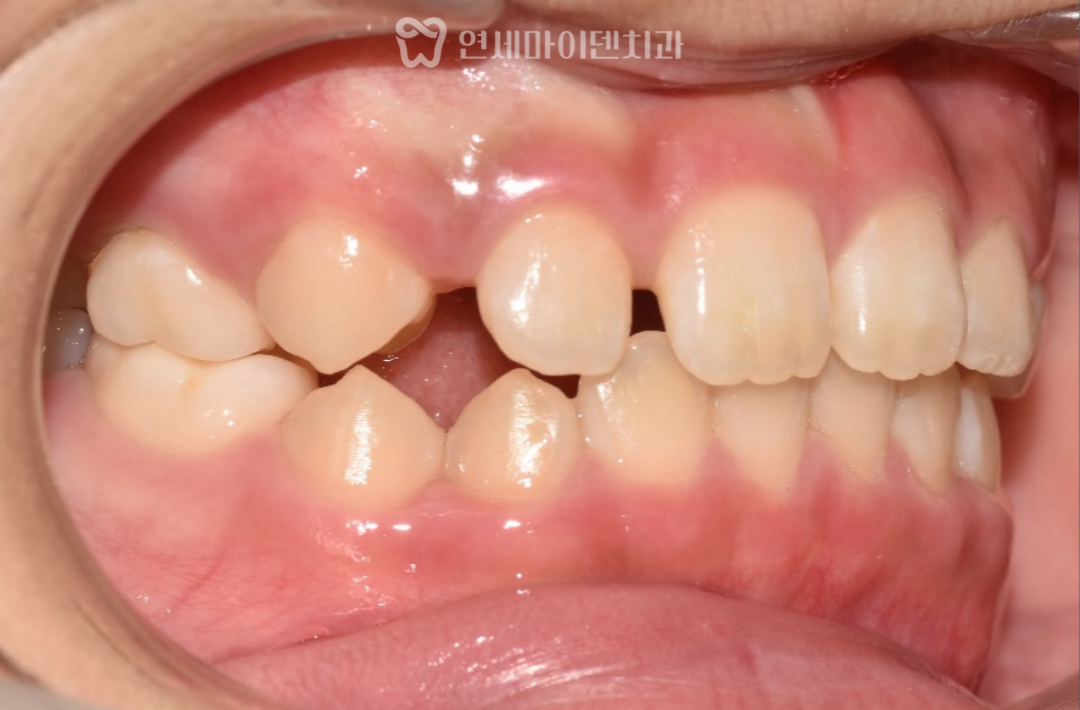

오늘은 매복된 송곳니 문제로 내원한 10살 어린이 환자분의

치아 교정 증례를 소개해드리고자 합니다.

이 환자분은 “양쪽 영구치 송곳니가 나오지 않아요.” 라는

주소로 방문하셨습니다.

한쪽 송곳니는 뼈 사이에 매복되어 있었고,

다른 한쪽 역시 공간 부족으로 자연맹출이 어려운 상태였습니다.

초기진단: 유치 조기 탈락과 송곳니 공간 부족

파노라마 사진을 통해 영구치 송곳니의 위치와 공간 문제를 확인하였습니다.

- 오른쪽 송곳니:

유치가 너무 일찍 빠지면서 공간이 닫혀,

영구치가 올라올 위치가 거의 사라진 상태였습니다. - 왼쪽 송곳니:

유치가 남아 있었지만 송곳니 크기 대비 공간 부족이 확인되었고,

특히 앞니 뿌리 사이로 매복되어 있어

앞니 뿌리 주변의 피질골도 일부 소실된 상황이었습니다.

이대로 송곳니가 자라게 되면

기존 앞니 뿌리를 밀어내어

발치까지 고려해야 하는 상황까지 이어질 수 있었습니다.